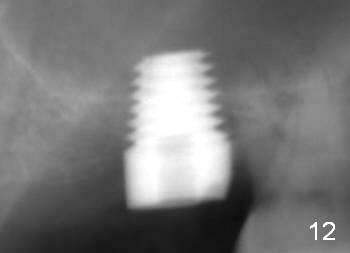

The patient returns for final restoration 22 months postop (Fig.12). Implant threads are embedded in the bone. Panoramic X-ray is taken after removal of perforated provisional and abutment. The implant remains asymptomatic 1 year post cementation (Fig.13) in spite of the fact that there appears to be no palatal plate (Fig.14 (1.5 years post cementation)). It is probably related to the thick palatal (P) gingiva. Periimplantitis develops 3 years post cementation and immediately post #15 implant 2nd removal. The implant is found to be palatal when #3 DO composite is placed (Fig.15). Oral hygiene appears to be difficult to maintain in spite of use of water pik. His diabetes is under control with Insulin.